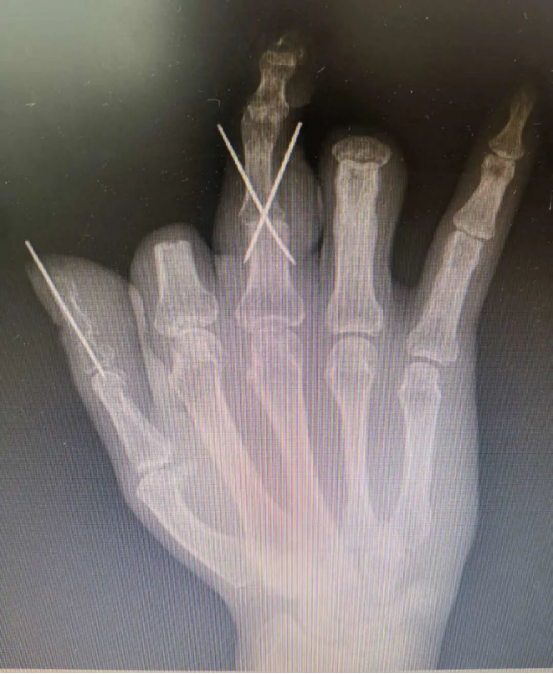

在放射科的支持下,醫院對患者雙手進行了CT三維重建,通過技術處理,虛擬出了患者缺失的手指,再使用新型材料打印出3D模型,模擬患者的斷指。通過對3D模型進行設計取樣,對患者右拇指、中指精準再造。

手術過程順利,由于3D打印技術的精準化輔助,兩根再造的手指外形美觀,不需要進行二期整形修復,足部供區創傷也達到最小化。又能用右手寫字、吃飯,陳先生很高興,“等這兩根手指恢復得差不多了,我馬上就來修復剩下兩根手指!”